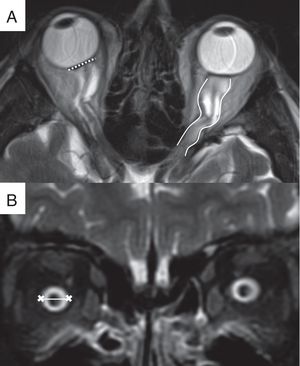

Se trata de un signo muy prevalente, con una sensibilidad variable y una especificidad cercana al 100% (fig. 2)13,16. La determinación de la presencia y el grado de alteración del globo ocular presentan marcada variabilidad interobservador, por lo que la cuantificación automatizada de la distorsión del globo ocular ha sido propuesta para mejorar la precisión diagnóstica17.

Hallazgos orbitarios. A) Imagen de resonancia magnética (RM), secuencia T2 FSE en el plano transversal, en la que se visualiza la distorsión de la morfología normal del globo ocular con aplanamiento de la esclera posterior bilateral (línea discontinua) así como la tortuosidad de los nervios ópticos en el plano horizontal (líneas continuas). B) Imagen de RM, secuencia STIR en el plano coronal, que demuestra la distensión de la vaina del nervio óptico tras el globo ocular (línea).

Mediante RM, las secuencias T2 con saturación de la grasa permiten evaluar correctamente la vaina del nervio óptico (NO) en la órbita18. En pacientes con papiledema se identifica un diámetro medio de la vaina del NO, medida tras el globo ocular, mayor que en pacientes sanos (7,54±1,05 mm frente a 5,52±1,11 mm respectivamente) (fig. 2)19,20. Este hallazgo presenta una sensibilidad del 45-66,7% y una especificidad del 82,1-95%, siendo la prevalencia del 65%14,21.

Tortuosidad del nervio ópticoEn la HII, la fijación del NO al anillo de Zinn y la esclera posterior del globo ocular producen elongación y tortuosidad intraorbitaria del NO. El desplazamiento puede producirse en el plano vertical o en el plano horizontal del nervio. La visualización de tortuosidad del NO en el plano vertical tiene mayor especificidad que en horizontal (fig. 2)18. Este hallazgo presenta una sensibilidad del 40% y una especificidad del 91%21.